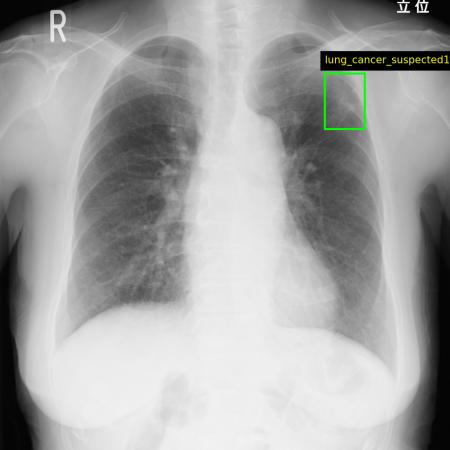

Callisto DataHub 2周年を記念し、専門医が作成した病変BBox付きの

肺がん疑いX線データセット 50症例と、病変セグメンテーション付きの

前立腺がんMRIデータセット(PI-RADS 4・5) 50症例を無料配布しています。前立腺がんMRIデータセットには、T1w, T2w, DWI, ADC, (あれば)DCEが含まれます。いずれも日本の医療施設由来で、所見文付き・商用利用可能なデータセットです。

肺がん疑いX線データセット